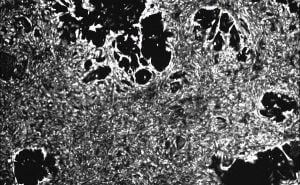

The primary cells obtained directly from the tissue of interest further can be used as in high-throughput assays like cell-based phenotypic analysis in order to measure the phenotypic output of cells i.e. further being helpful to predict acute toxicity like cellular proliferation, plasma membrane permeability, ATP content analysis, etc. As a matter of fact, great literature is available on the application of primary cells in different cell-based assays that can further lead to drug development and toxicological analysis. However, it should be noted that these simple cytotoxicity assays are largely been used for a quite a long time with partial success. In this regard, an important consideration should be offered to the type of cell preference, it culture efficiency as well as viability. Cell types that is more physiologically relevant like an animal or human primary cells are found to be more in demand than others.